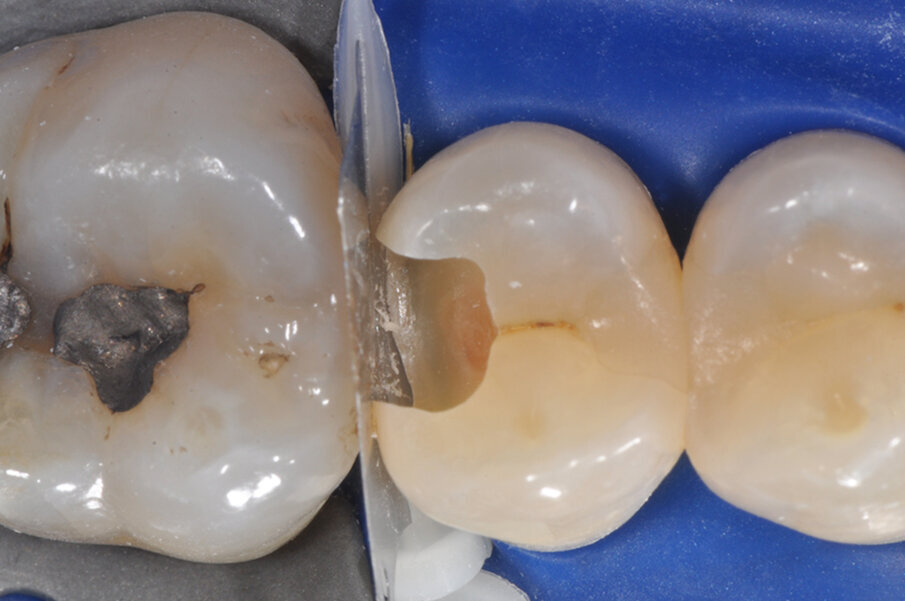

Viene posizionata una matrice Fusion FX175 e inserito un cuneo Fusion FXOR da vestibolare, per favorire la chiusura della matrice nell’angolo tra gradino cervicale e parete assio-pulpare vestibolare, resa difficile dalla rotazione dell’elemento 1.5 (Fig. 6). Si posiziona l’anello separatore FX400 - si noti il perfetto adattamento della matrice alle pareti assiali e al gradino cervicale. Quest’ultimo grazie soprattutto all’azione delle alette in silicone del cuneo (Fig. 7). Un’altra inquadratura evidenzia la profondità della cavità pulita (Fig. 8).